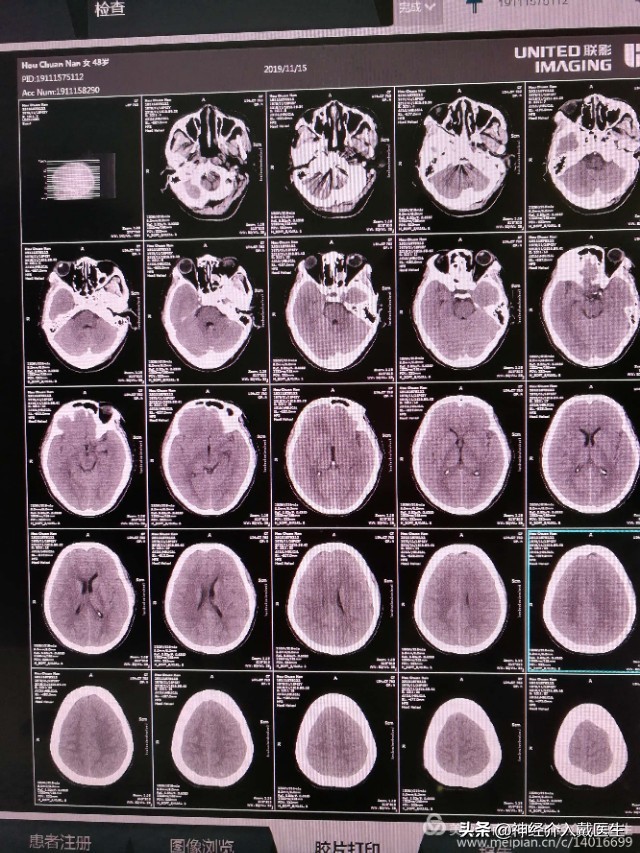

入院时候头部CT:四脑室少量出血,如果不仔细看CT片子,可能还发现不了。是什么原因引起的四脑室出血?首先考虑血管性病变,首选还是脑血管造影。

术后仍然剧烈头疼,复查头部CT排除颅内迟发出血。